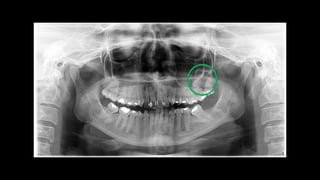

Os ceratocistos odontogênicos exibem uma área radio lúcida, com margens escleróticas

frequentemente bem definidas. Lesões grandes, particularmente no corpo posterior e no

ramo da mandíbula, podem se apresentar multiloculadas.

Os ceratocistos odontogênicosexibem uma área radio lúcida, com margens escleróticas frequentemente bem definidas. Lesões grandes, particularmente no corpo posterior e no ramo da mandíbula, podem se apresentar multiloculadas.